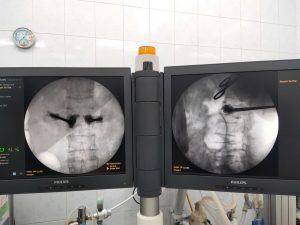

Thông tin thêm về kỹ thuật can thiệp này, BSCKII Đàm Quang Thịnh cho biết: Phẫu thuật tạo hình thân đốt sống bằng xi măng sinh học là một phẫu thuật ít xâm lấn. Xi măng sinh học được bơm vào thân đốt sống với mục đích giảm đau, nâng chiều cao thân đốt sống, tái khôi phục đường cong sinh lý và tăng độ vững cho cột sống. Tại Bệnh viện Bắc Thăng Long phẫu thuật tạo hình thân đốt sống bằng xi măng sinh học được thực hiện hằng ngày, một cách thường quy dưới sự hỗ trợ của hệ thống máy móc hiện đại nên hình ảnh rõ nét giúp phẫu thuật viên thao tác dễ dàng, chính xác, hạn chế tai biến, biến chứng có thể xảy ra cho người bệnh.